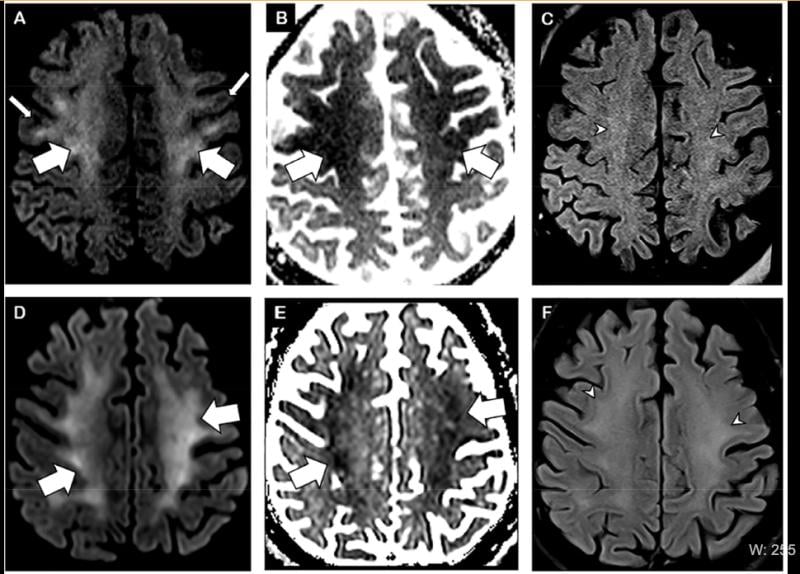

This photo gallery shows the variety of radiological presentations of COVID-19 (SARS-CoV-2) in medical imaging, including computed tomography (CT), radiograph X-rays, ultrasound, echocardiograms and magnetic resonance imaging (MRI). The radiology images show examples of typical COVID pneumonia in the lungs and the numerous complications the virus causes in the body in multiple organs, including the brain, kidneys, heart, abdomen and vascular system.